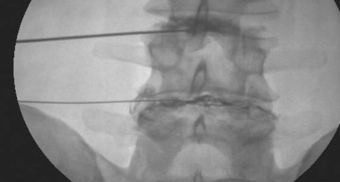

Colocación de Agujas

Discografía L3, L4 y L4, L5 AP